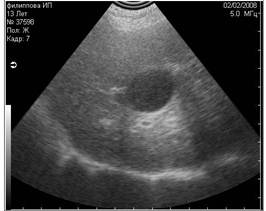

2. Эхоакустическое псевдоусиление

Этот артефакт возникает позади структур, слабо поглощающих ультразвук, т.е. позади содержащих жидкость объектов (мочевой пузырь, желчный пузырь, кисты и пр.). В некотором смысле он противоположен артефакту теней (1;4;5).

Знание этого феномена помогает в подтверждении жидкостной природы сканируемого объекта. Классическим примером является нормальное эхоакустическое псевдоусиление, появляющееся в паренхиме печени позади желчного пузыря. Эхоакустическое псевдоусиление имеет решающее значение при дифференциальной диагностике кист от новообразований с низкой эхогенностью.

![]() |

|

Рис. 18. Артефакт периферического эхоакустического усиления . Звуковая волна слева практически не ослабляется, проходя через наполненный жидкостью пузырь, поэтому область позади него остаётся яркой. Звуковая волна справа, проходящая через паренхиму, ослабляется и затухает. |

Рис. 19. Артефакт периферического усиления, возникший позади желчного пузыря. |